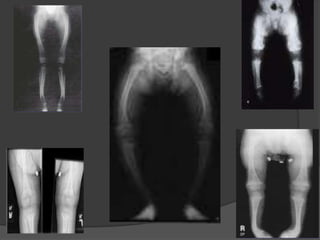

Clinical signs

Knock knee deformity

(genu valgum)

Bowleg deformity

(genu varum)

A teenage male with rickets.

Note deformities of legs (bow legs)

and compromised height.